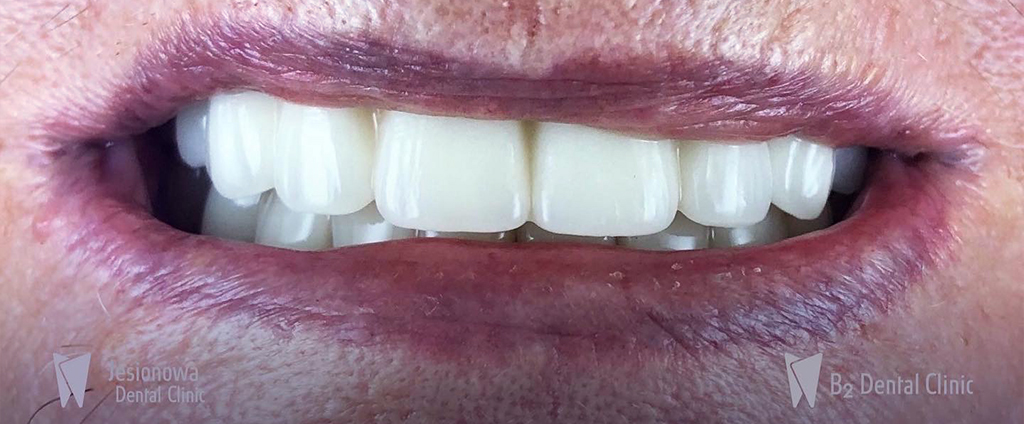

Ostateczna praca protetyczna może być: zdejmowana, przymocowana na stałe, wykonana z akrylu, cyrkonu lub porcelany na podbudowie metalowej. Dowiedz się więcej na temat mostów protetycznych

5. Oddanie pracy

Ostatnim etapem 1 dniowej wizyty jest założenie Twoich nowych zębów i przymocowanie ich do implantów. Odzyskasz zdrowy i piękny uśmiech w tym samym dniu (dotyczy mostów tymczasowych).